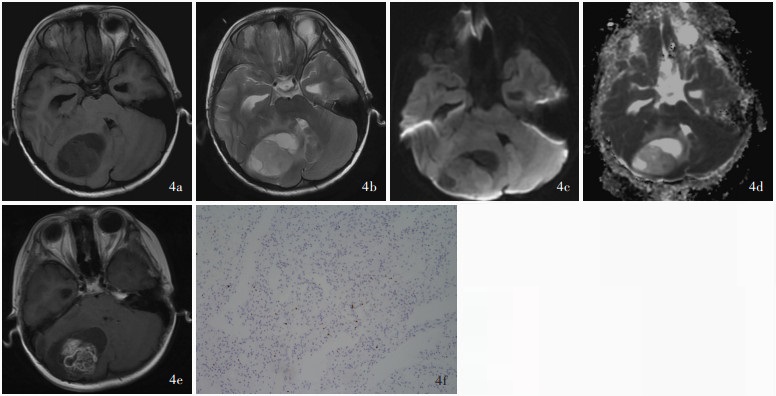

目的: 探讨儿童后颅窝常见肿瘤的影像学诊断与鉴别诊断方法,并按照先定位诊断再定性诊断的思路,基于DWI是否弥散受限提出儿童后颅窝常见肿瘤的诊断流程图。方法: 共纳入2021年1月至2024年1月在复旦大学附属华山医院予以手术切除的118例儿童后颅窝肿瘤患者,均行头部CT和MRI检查,并据此进行术前定位和定性诊断,分别以术中所见和术后病理学检查为诊断“金标准”,判断术前定位诊断和定性诊断的准确性;再基于DWI是否弥散受限提出儿童后颅窝常见肿瘤的诊断流程图。结果: 共118例后颅窝肿瘤患儿定位和定性诊断为第四脑室肿瘤计41例,包括髓母细胞瘤27例、毛细胞型星形细胞瘤7例、室管膜瘤5例、脉络丛乳头状瘤1例、形成菊形团的胶质神经元肿瘤1例;脑干肿瘤38例,包括弥漫性中线胶质瘤,H3 K27变异型24例、毛细胞型星形细胞瘤5例、海绵状血管瘤3例、儿童型弥漫性高级别胶质瘤(倾向弥漫性中线胶质瘤,H3野生型)2例、节细胞胶质瘤2例、非典型性畸胎样/横纹肌样肿瘤1例、儿童型弥漫性低级别胶质瘤1例;脑桥小脑角肿瘤计9例,包括毛细胞型星形细胞瘤3例、胆脂瘤2例、髓母细胞瘤1例、弥漫性中线胶质瘤,H3 K27变异型1例、毛细胞黏液型星形细胞瘤1例、尤文肉瘤1例;小脑肿瘤计30例,包括毛细胞型星形细胞瘤15例、髓母细胞瘤7例、海绵状血管瘤2例、室管膜瘤1例、儿童型弥漫性低级别胶质瘤1例、儿童型弥漫性高级别胶质瘤(倾向弥漫性中线胶质瘤,H3野生型)1例、胚胎发育不良性神经上皮肿瘤1例、错构瘤1例和肾外横纹肌样瘤小脑转移瘤1例。定位诊断,术前CT的定位诊断准确率为93.22%(110/118),MRI的定位诊断准确率达100%(118/118)。定性诊断,74例(62.71%)患儿定性诊断准确,23例(19.49%)诊断笼统,21例(17.80%)诊断错误。儿童后颅窝肿瘤的影像学鉴别诊断集中于髓母细胞瘤、毛细胞型星形细胞瘤、室管膜瘤、弥漫性中线胶质瘤,H3 K27变异型。位于脑干外的髓母细胞瘤、毛细胞型星形细胞瘤和室管膜瘤的DWI弥散受限发生率分别为100%(35/35)、4%(1/25)和5/6,3种肿瘤之间差异有统计学意义(Z=-5.601,P=0.000);位于脑干的弥漫性中线胶质瘤,H3 K27变异型和毛细胞型星形细胞瘤的DWI弥散受限发生率为79.17%(19/24)和1/5,两种肿瘤之间差异亦有统计学意义(Fisher确切概率法:P=0.038)。结论: 儿童后颅窝肿瘤早期诊断较为困难,DWI是鉴别诊断的重要依据,基于DWI是否弥散受限提出的儿童后颅窝常见肿瘤诊断流程图有望提高术前诊断的准确性。

Objective: To investigate the imaging diagnosis and differential diagnosis methods for common tumors in the posterior fossa of children, and to propose a flow chart for the diagnosis of common tumors in the posterior fossa of children based on the limited diffusion of DWI according to the idea of localization diagnosis followed by qualitative diagnosis. Methods: A total of 118 pediatric patients with posterior fossa tumors who underwent surgical resection in Huashan Hospital, Fudan University from January 2021 to January 2024 were enrolled, and all of them underwent head CT and MRI examinations, and preoperative localization diagnosis and qualitative diagnosis were carried out accordingly. Then, based on whether DWI was diffusion limited, a flow chart for the diagnosis of common tumors in the posterior fossa of children was proposed. Results: A total of 118 children with posterior fossa tumors were localization and qualitatively diagnosed, including 41 cases of fourth ventricular tumors, including medulloblastoma (27 cases), pilocytic astrocytoma (7 cases), ependymoma (5 cases), choroid plexus papilloma (one case), and rosette-forming glioneuronal tumor (RGNT, one case). There were 38 cases of brainstem tumors, including 24 cases of diffuse midline glioma, H3 K27-altered, 5 cases of pilocytic astrocytoma, 3 cases of cavernous hemangioma, 2 cases of pediatric-type diffuse high-grade glioma (prone to diffuse midline glioma, H3 wild type), 2 cases of ganglio glioma, one case of atypical teratoid/rhabdoid tumor (AT/RT), and one case of pediatric-type diffuse low-grade glioma. There were 9 cases of cerebellopontine angle (CPA) tumors, including 3 cases of pilocytic astrocytoma, 2 cases of cholesteatoma, one case of medulloblastoma, one case of diffuse midline glioma, H3 K27-altered, one case of pilomyxoid astrocytoma, and one case of Ewing sarcoma. There were 30 cases of cerebellar tumors, including 15 cases of pilocytic astrocytoma, 7 cases of medulloblastoma, 2 cases of cavernous hemangioma, one case of ependymoma, one case of pediatric-type diffuse low- grade glioma, one case of pediatric-type diffuse high- grade glioma (prone to diffuse midline glioma, H3 wild type), one case of dysembryoplastic neuroepithelial tumor (DNT), one case of hamartoma, and one case of extrarenal rhabdomyomatoid tumor cerebellar metastases. Localization diagnosis, the accuracy of preoperative CT was 93.22% (110/118), while the accuracy of preoperative MRI was 100% (118/118). Qualitative diagnosis, 74 cases (62.71%) had accurate qualitative diagnosis, 23 cases (19.49%) had general diagnosis, and 21 cases (17.80%) had wrong diagnosis. The imaging differential diagnosis of posterior fossa tumors in children focuses on medulloblastoma, pilocytic astrocytoma, ependymoma, and diffuse midline glioma, H3 K27-altered. The incidence of limited diffusion of DWI in medulloblastoma, pilocytic astrocytoma and ependymoma outside the brainstem was 100% (35/35), 4% (1/25) and 5/6, and the difference among the three tumors was statistically significant (Z =-5.601, P = 0.000). The incidence of limited diffusion of DWI in diffuse midline glioma, H3 K27-altered and pilocytic astrocytoma in the brainstem was 79.17% (19/24) and 1/5, and the difference between the two tumors was also statistically significant (Fisher's exact possibility: P = 0.038). Conclusions: The early diagnosis of posterior fossa tumors in children is difficult, and DWI is an important basis for differential diagnosis.